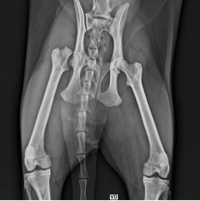

Olá, me chamo Emanuelle. Meu gatinho caiu da janela e acabou quebrando a pata, precisará fazer uma cirurgia (ou amputar a pata) que sairá no valor de R$3.000,00 porém eu não tenho condições de pagar, então criei essa Vakinha para arrecadar esse valor. Darkin é um gatinho preto muito amoroso e carente, tem 1 ano e é a melhor coisa que já aconteceu em minha vida, por favor nos ajudem, qualquer valor é bem-vindo!! :)